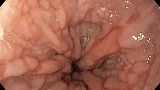

Публикации из социальных сетей: “Cobblestone esophagitis” (эзофагит со слизистой булыжной мостовой)

“Cobblestone esophagitis” (эзофагит со слизистой булыжной мостовой) - редкая эндоскопическая находка и ассоциируется с эозинофильным эзофагитом, кандидозом и пищеводом Барретта у взрослых. Он также может быть найден при тяжелом рефлюкс-эзофагите, вторичен к дистальной обструкции гастроинтестинального тракта. В нашем случае - это пациент после с 9-летним стажем бандажирования кардиального отдела желудка, признаками дуоденостаза, фундальной эрозивной гастропатией, расширением пищевода и уровнем жидкости в нем при горизонтальном положении, грыжи ПОД, эрозивно-язвенном дистальном эзофагите.. Пациент просто пришел удалить полип в прямой кишке и заодно посмотреть, что творится в желудке.... Ацетообеление+NBI+биопсия. ИПП на 3-4 мес и повтор для решения о Барретте.